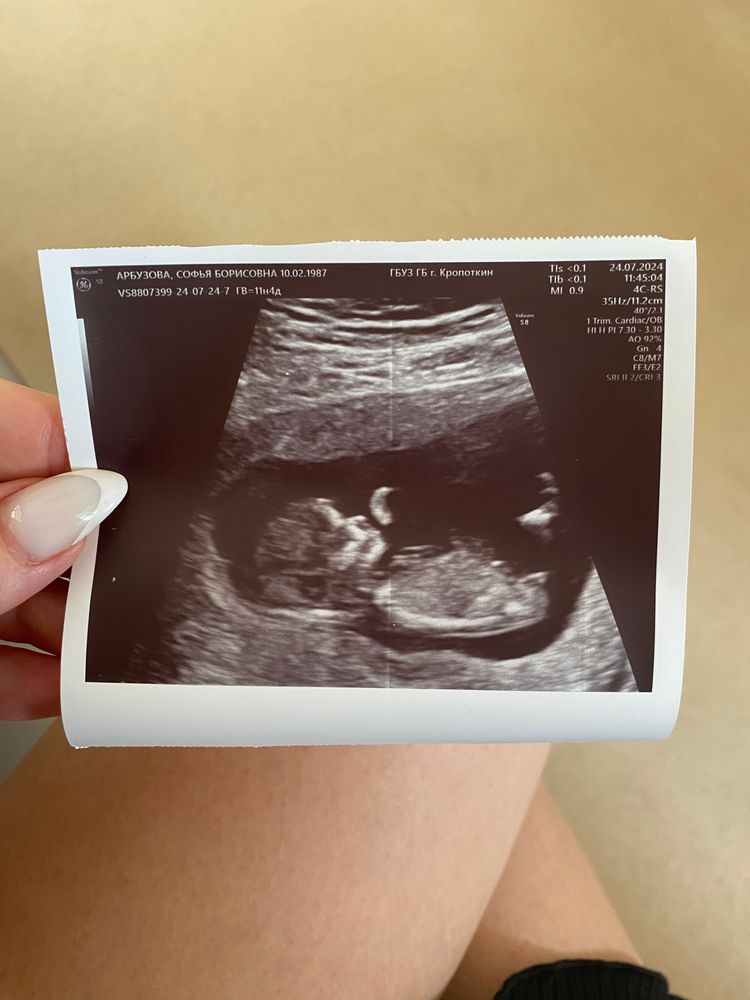

Мальчик или девочка???

Такой профиль красивый) маленький Человек 😍

Видите, бугорок четко параллелен позвоночнику?)) Девочка точно)) Я с такой же фоткой своей 3й дочки неделю здесь просидела, в надежде найти там мальчика 😂

По полосочке точно девочка

Я девочку вижу ,персик 😀

Какая фотка классная! 😍Такой маленький милый человечек🤩. Я тоже за девочку🤞 Софья, а мужу и мальчишкам рассекретилась?

Девочка, у моей также торчало))